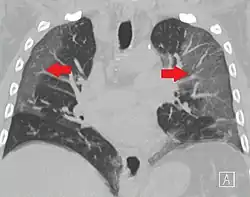

El 12 de enero de 2020, las autoridades chinas habían confirmado la existencia de 41 personas infectadas con el nuevo virus, quienes comenzaron a sentir síntomas entre el 8 de diciembre de 2019 y el 2 de enero de 2020, los cuales incluían: fiebre, malestar, tos seca, dificultad para respirar y fallos respiratorios;[43] también se observaron infiltrados neumónicos invasivos en ambos pulmones observables en las radiografías de tórax.[44]

La revista The Lancet publicó el 24 de enero de 2020 un estudio de los primeros 41 casos de pacientes ingresados (en hospital de Wuhan) con el diagnóstico confirmado, desde el 16 de diciembre de 2019 al 2 de enero de 2020.[107] De ellos, menos de la mitad tenían enfermedades subyacentes, entre ellas diabetes, hipertensión y enfermedad cardiovascular. Los síntomas comunes al inicio de la enfermedad fueron fiebre, tos seca y mialgias o fatiga; los síntomas menos comunes fueron la producción de esputo, cefalea, hemoptisis y diarrea. La disnea se desarrolló en 22 de 40 pacientes (55 %), con una mediana del tiempo desde el inicio de la enfermedad hasta la disnea de ocho días. Presentaron linfopenia 26 de 41 pacientes (63 %). Todos los pacientes tuvieron neumonía con hallazgos anormales en la TC de tórax.[117]

La radiología torácica (bien por radiografía, tomografía computerizada o ecografía) puede ayudar al diagnóstico de COVID-19 e identificar o descartar complicaciones pulmonares.[172]